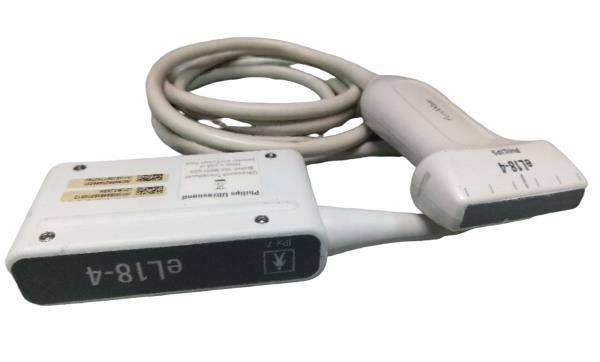

The Laptop Ultrasound Scanner combines cutting-edge technology with portability to enhance your medical practice. This device allows for high-quality ultrasound imaging, ensuring that healthcare professionals can provide accurate diagnoses. Additionally, it features a Transvaginal probe that delivers detailed views of internal structures, making it indispensable for gynecological examinations. Because of its sophisticated design, you can easily operate it in various clinical settings.

Advanced Technology for Superior Imaging